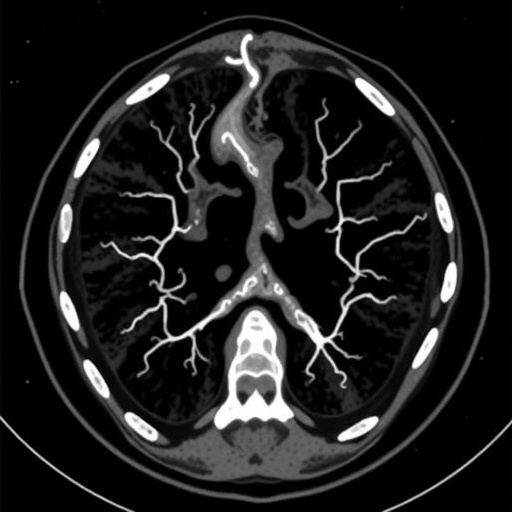

CT angiography has emerged as a preferred imaging modality because of its ability to provide detailed, high-resolution images of blood vessels. Unlike traditional angiography, which is more invasive and involves catheterization, CT angiography employs non-invasive techniques that can swiftly display the anatomy of the vascular structure. The capability to visualize the vascular system in three dimensions adds another layer of analysis that enhances the diagnostic process. However, its effectiveness in measuring flow parameters, especially in dynamic conditions within a phantom model of carotid stenosis, raises essential questions regarding its reliability compared to other standard techniques.

The study employed a sophisticated hemodynamic phantom model simulating carotid stenosis, allowing researchers to replicate various conditions reflecting real-life scenarios. This innovative model facilitated precise measurements of blood flow dynamics, which is critical for validating the performance of the imaging techniques being compared. Through this approach, the researchers aimed to establish correlations between the imaging data obtained from CT angiography and the hemodynamic parameters assessed by duplex sonography. The implications of such findings could enhance clinical decision-making, leading to better patient outcomes and improved management strategies for carotid artery diseases.